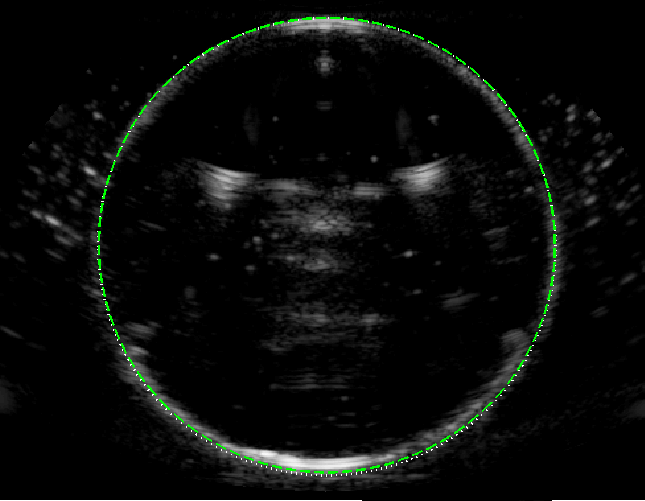

Experimental B-mode images (with curved array) of the circular test object are shown in figure 5, alongside the ray model predictions, for following 3 speed of sound scenarios.

(a) v2<v1subscript𝑣2subscript𝑣1v_{2}<v_{1}: Here we consider v1=1540subscript𝑣11540v_{1}=1540 m s-1 (ethanol-water mixture) and v2=1490subscript𝑣21490v_{2}=1490 m s-1 (water), giving v2/v1=0.97subscript𝑣2subscript𝑣10.97v_{2}/v_{1}=0.97. No geometric distortion is evident at the near face but the far face is shifted away from the transducer, in good agreement with the ray model (dashed green line).

(a)                                  (b)                                  (c)

Refer to caption Refer to caption Refer to caption

Figure 5: B-mode images of the circular object of speed v2subscript𝑣2v_{2} (imaged from above in a liquid with speed v1subscript𝑣1v_{1}), with the ray model superimposed (green dashed line). (a) v2=1490subscript𝑣21490v_{2}=1490 m s-1 and v1=1540subscript𝑣11540v_{1}=1540 m s-1, giving v2/v1=0.968subscript𝑣2subscript𝑣10.968v_{2}/v_{1}=0.968. (b) v2=1100subscript𝑣21100v_{2}=1100 m s-1 and v1=1540subscript𝑣11540v_{1}=1540 m s-1, giving v2/v1=0.71subscript𝑣2subscript𝑣10.71v_{2}/v_{1}=0.71. (c) v1=1490subscript𝑣11490v_{1}=1490 m s-1 and v2=1540subscript𝑣21540v_{2}=1540 m s-1, giving v2/v1=1.034subscript𝑣2subscript𝑣11.034v_{2}/v_{1}=1.034.